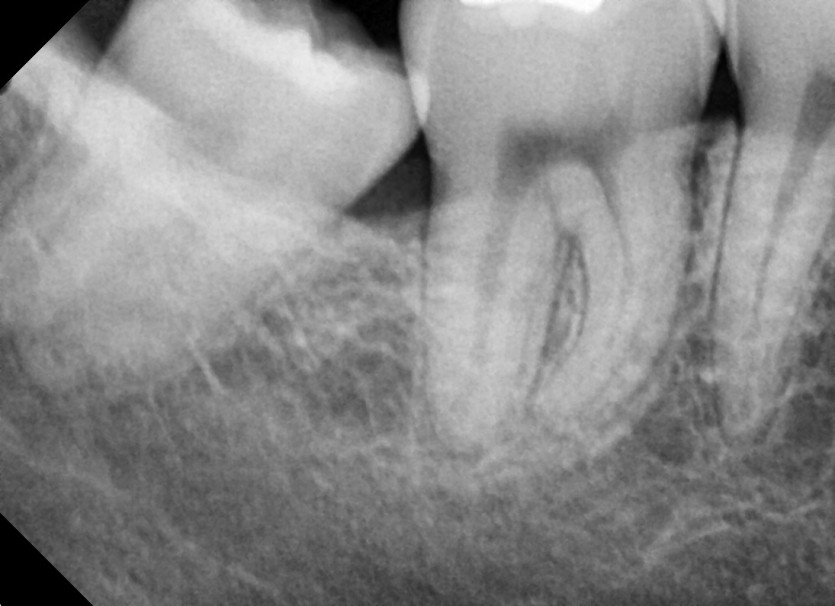

#18,48 사랑니 발치

구강 외과 전문의가 당일 발치했습니다.